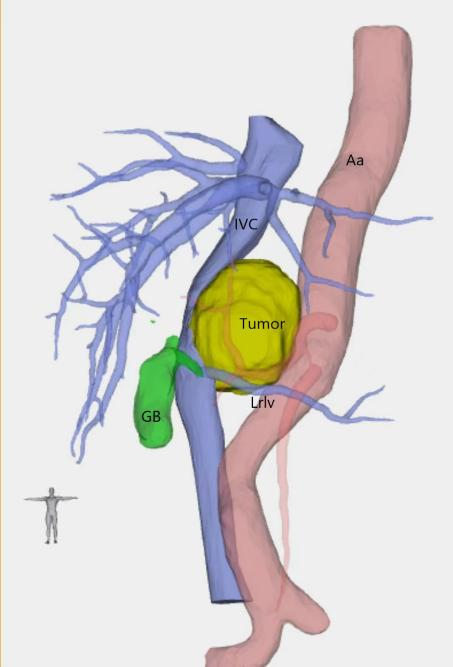

(视频1.完全腹腔镜下后腹膜副神经节瘤切除)

(后腹膜副神经节瘤术前三维重建结果)